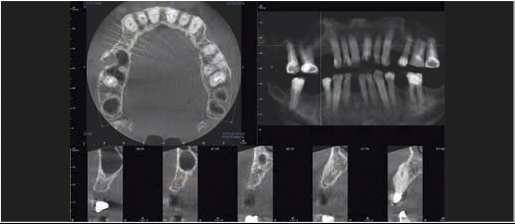

Tomografia komputerowa jest niezastąpiona w planowaniu leczenia implantologicznego i chirurgicznego. W wielu przypadkach pozwala uniknąć powikłań podczas leczenia kanałowego jeszcze przed jego rozpoczęciem. Wysokiej rozdzielczości badanie mikroCBCT (endoCBCT) precyzyjnie obrazuje architekturę systemu kanałowego zęba. Na jego podstawie lekarz może ocenić ilość kanałów, ich krzywiznę oraz ewentualne połączenia.

Precyzyjna diagnostyka z polem obrazowania 5 x Ø5 cm i rozdzielczością 85 μm (TRYB ENDO).

Szczegółowa analiza systemu kanałowego zębów oraz tkanek przyzębia.

Pole obrazowania 8 x Ø8 cm (górny/dolny wyrostek zębodołowy wraz z okolicą przywierzchołkową oraz przekrojem poprzecznym zatoki) dawka promieniowania to jedyne 16 μSv w trybie DRT. Szczególnie przydatne w chirurgii jamy ustnej.

Zredukowana wysokość skanu do 6 x Ø8 cm zapewnia pełną wartość diagnostyczną w przypadku obrazowania jednej szczęki.

Cztery różne pola obrazowania zapewniają niezawodną diagnostykę 3D w całym obszarze jamy ustnej. Zapewniają one precyzyjne dopasowanie, odpowiednie do wskazań a także uniwersalne możliwości zastosowania w codziennej praktyce – od endodoncji, poprzez implantologię do chirurgii jamy ustnej.